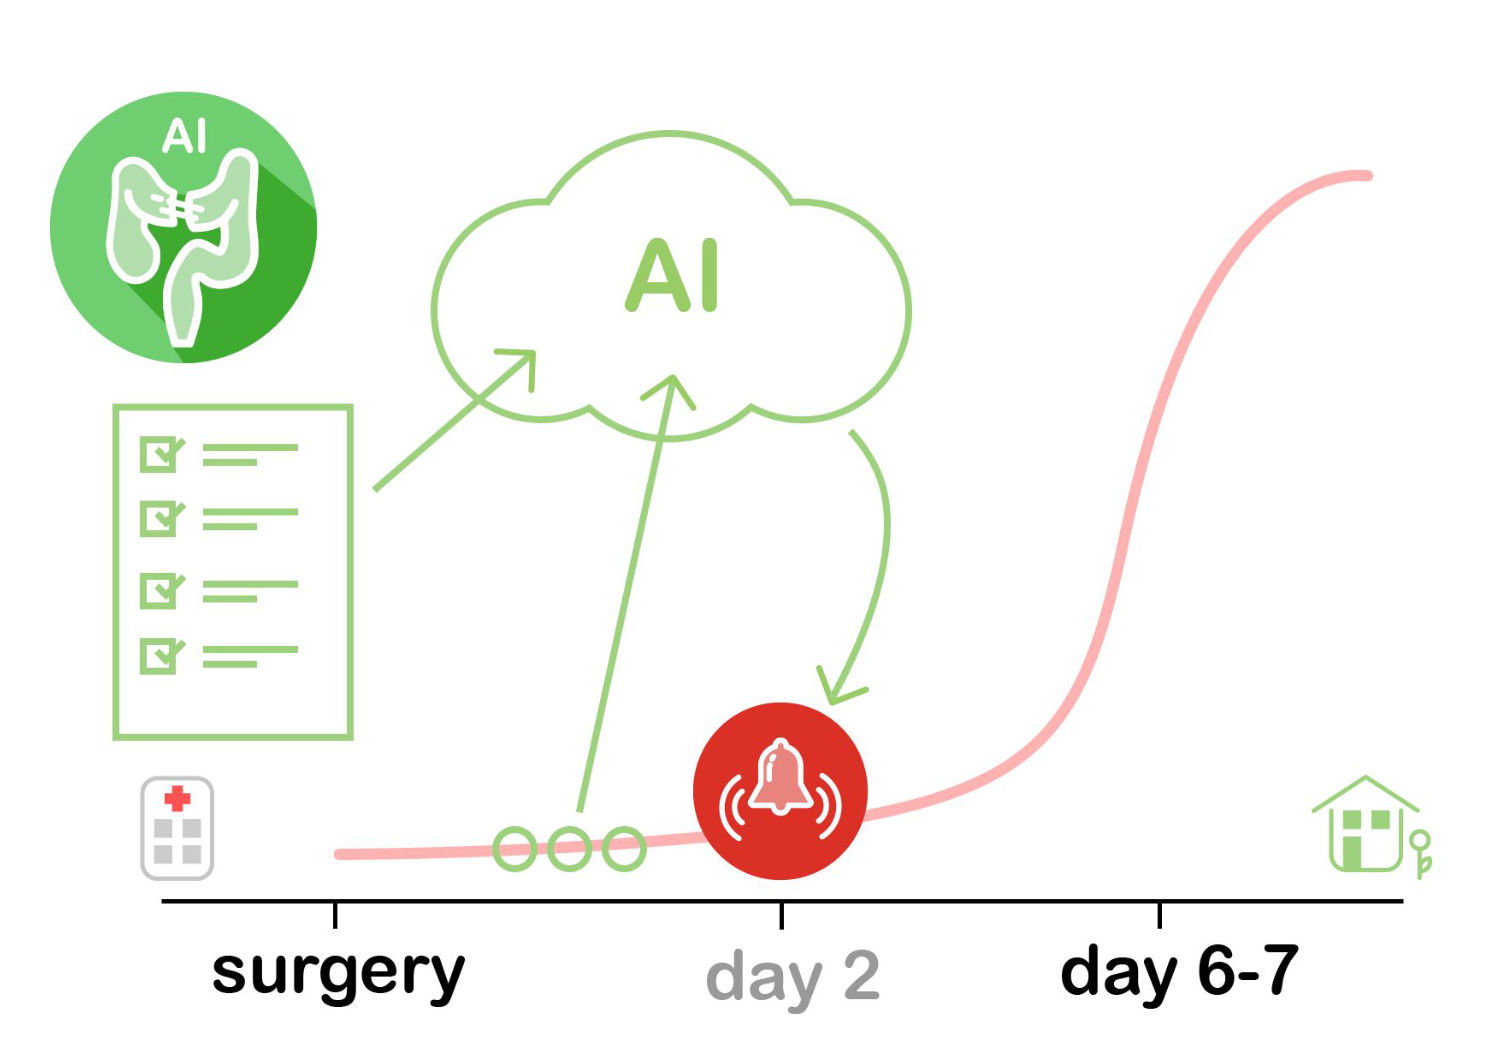

CASSANDRA - Clinical ASSist AND aleRt Algorithm

CASSANDRA - Clinical ASSist AND aleRt Algorithm

An application for such a ML based alert algorithm (CASSANDRA) can be the preoperative risk stratification of patients with the intention to uncover previously unidentified patterns and therefore enable an automatic assessment. Additionally, if such a system is continuously fed information during an in-patient stay, real-time predictions of complications can be possible. At the moment we are in the development of ML based complication recognition mechanisms and are planning an implementation of real-time alert algorithms in the near future.